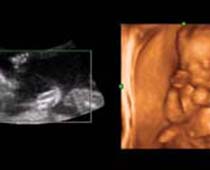

- 3D Fetal Limbs Ultrasound Scan Photos

- The Clinical Advantages of 3D and 4D Ultrasound

- Definition and Features of Four Dimensional Ultrasound

- Uses of 4D Ultrasound scan